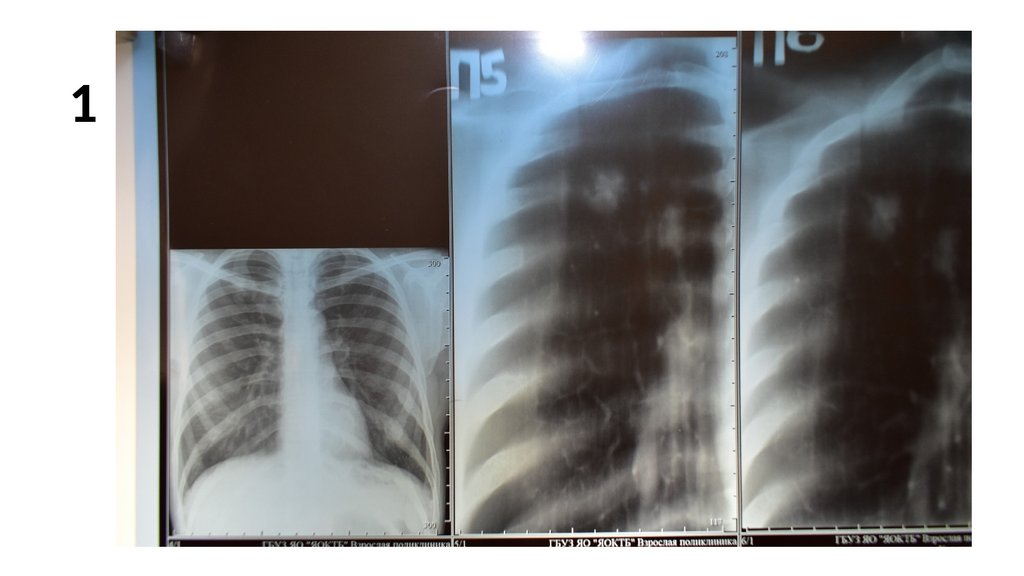

1.

Оценка рентгенограммы

Описать одну рентгенограмму. Номер рентгенограммы соответствует

вашему номеру в журнальном списке группы.

Схема описания:

1. Опишите представленные снимки, выделите основной рентгенологический

синдром.

2. Имеются ли признаки туберкулеза на данных снимках? Если да,

перечислите их.

3. При наличии признаков туберкулеза определите форму, фазу процесса,

укажите возможные осложнения.

4.Составьте дифференциально-диагностический ряд, укажите наиболее

вероятные заболевания.

5. Какие методы верификации диагноза применимы в данном случае.